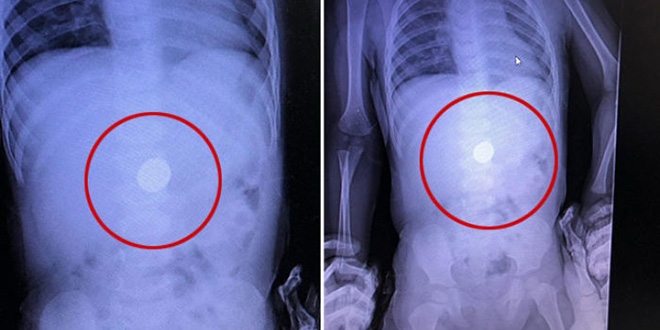

Röntgende tespit edildi, doğal yolla çıkması beklenecek

Oyun oynarken para yuttuğu röntgende tespit edildi